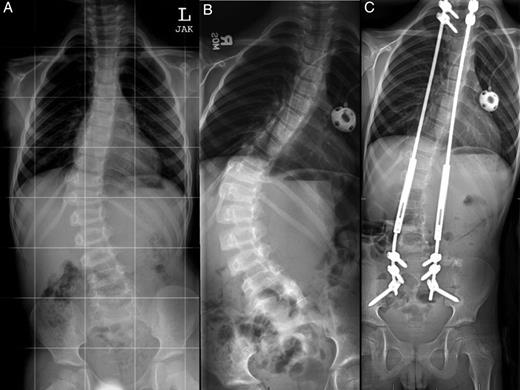

Anterior-posterior (AP) plain films of the spine at the time of diagnosis (A), after curve progression (B) and 1 year after growing rod insertion (C). Measured Cobb angles were 32 degrees (A), 64 degrees (B) and 22 degrees (C), respectively.